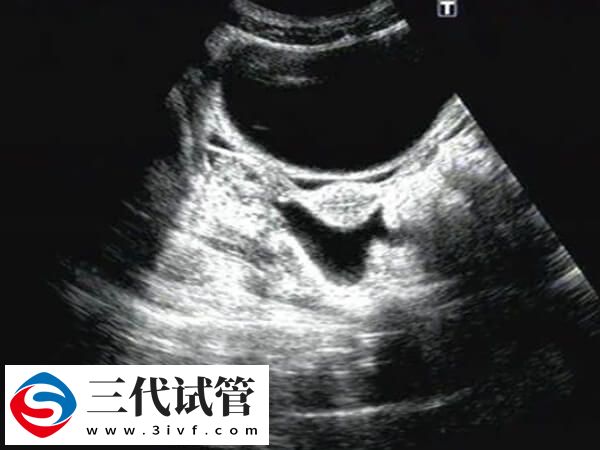

一般女性在试管鲜胚移植40天左右出现宫腔积液的情况较为常见,可能是胚胎植入子宫内膜导致的积液现象,也可能是其它原因,至于出现积液后多久干净,对此感兴趣的可以参考下列内容:

患者在试管鲜胚移植40天检查发现宫腔有积液,若是宫腔积液量较少,主要由生理因素引起的,那么通常不需要进行治疗,会自行消失,一般可能需要7-10天左右能使宫腔积液自行吸收。

试管鲜胚移植40天宫腔有积液,若是因怀孕后体内的黄体功能不足,孕激素水平也比较低,导致的宫腔积液的情况,或是宫腔存在感染现象而出现宫腔积液,那么可能需要1-2个月才能让积液逐步减小或消失。

试管囊胚移植40天宫腔有积液的干净时间不可一概而论,还需要根据实际情况进行判断,毕竟每个患者身体情况不同多样积液消失时间也会有差异,建议出现宫腔积液的患者,应该定期进行超声检查,监测积液的变化,然后根据医生的建议进行适当的保胎措施。